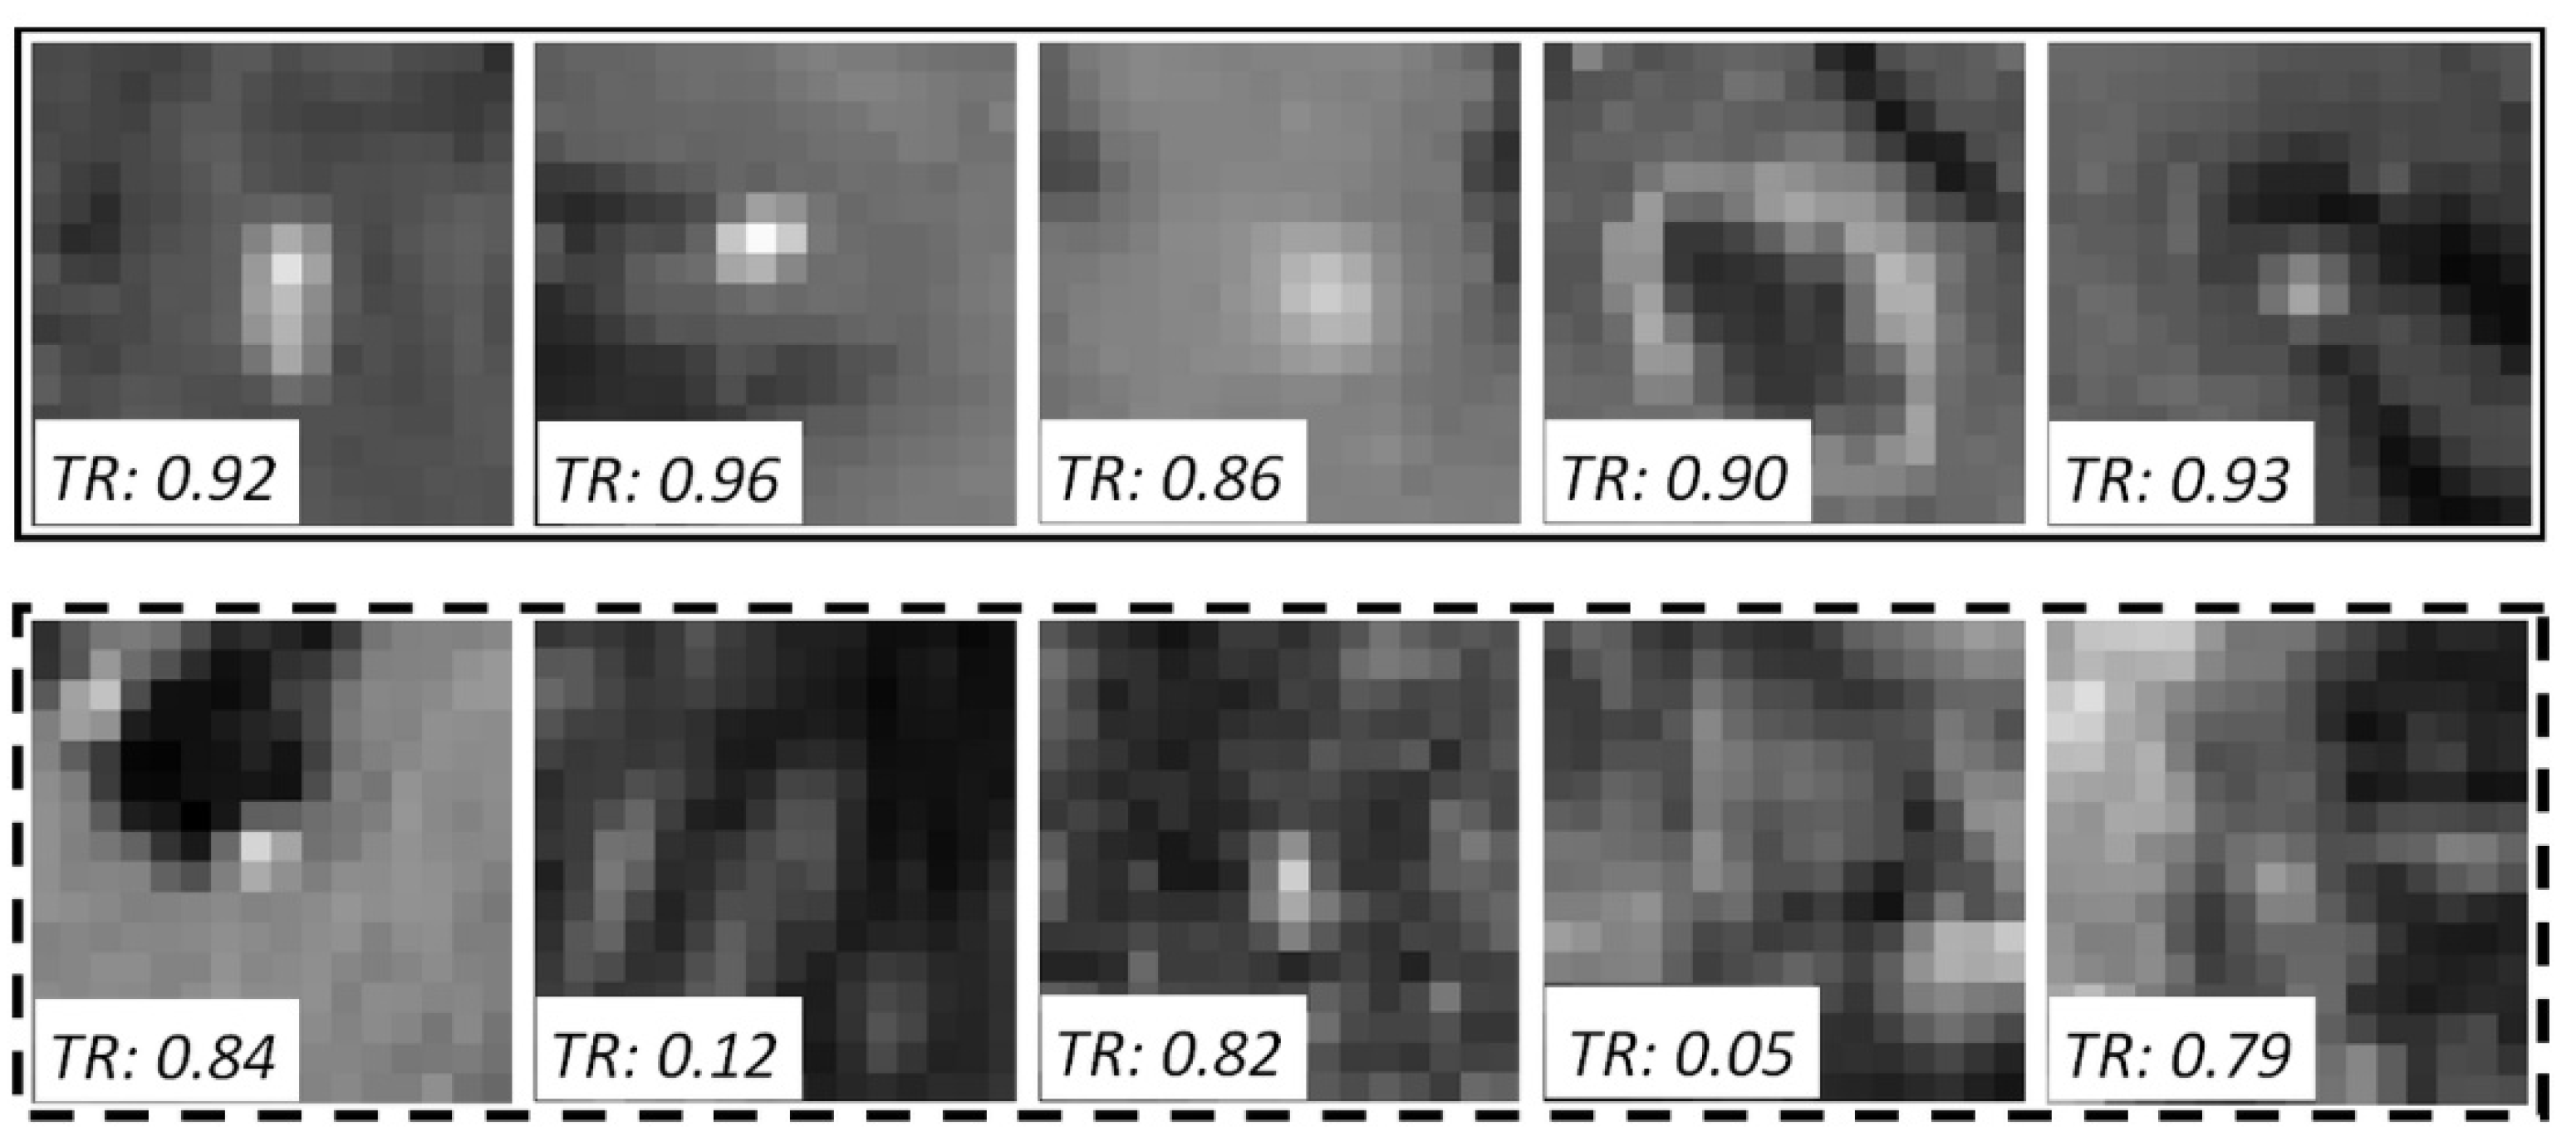

2.3. Technical Contribution: Sensitivity-Based NS Algorithm

3.2.1. Teacher Model Sensitivity